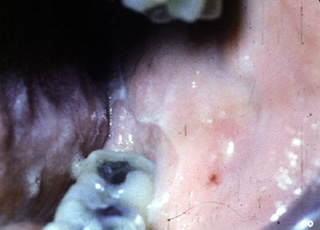

Este paciente, es una mujer mexicana de 49 años de edad que  presentó ulceraciones orales por un período de un año. Se trató sin éxito con corticoides en varias ocasiones. La biopsia no determinó un diagnóstico.

Durante la anamnesis ella había tomado un diurético, para el tratamiento de la  hipertensión durante los últimos cinco años. Cuando se cambió el diurético y se administró corticoides  el problema se resolvió en poco tiempo. La terapia antihipertensiva es obviamente una de las causas primarias del la erupción liquenoide necrotizante.

Aquí hay otra área afectada en el paciente presentado en la imagen anterior